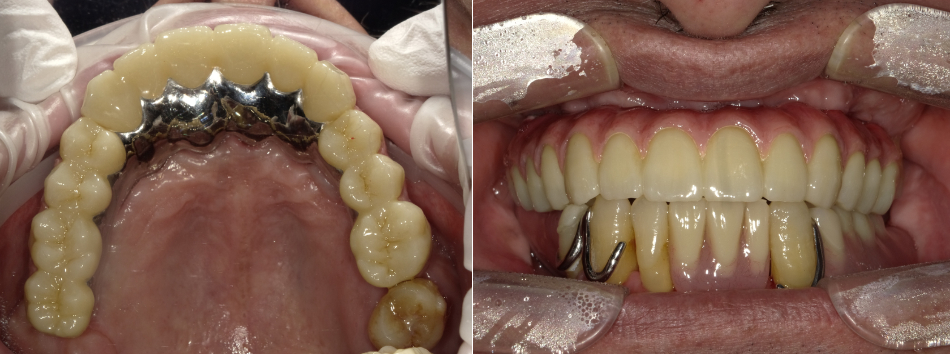

After

症例詳細

・主訴:歯がなくてうまく噛めない

・治療内容:AGCと言われている茶筒の原理を利用したセメントを用いずに審美的に優れている術者可撤式のBrを製作しました。

・院長コメント:上顎の歯槽骨の吸収も激しかったためGBR・サイナスリフトも行っております。術者可撤式といって、メンテナンス時に外して清掃、再セットが容易に行えるというメリットもあります。

・治療費(税込):3,850,000円

・治療期間・通院回数:12ヶ月・40回

・リスク:全顎治療となりますので通院回数が増えてしまいます。また骨の状態にもよりますが、骨増生とインプラント埋入手術を別に行う場合には治療期間もより長期となってしまいます。